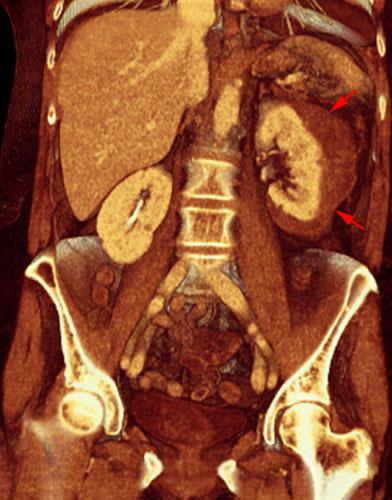

Hematoma subcapsular

VR seccional. Visión coronal anterior. Serie contrastada en fase venosa que muestra una inversión de las densidades, visualizándose el hematoma subcapsular (flechas) mas hipodenso que el parenquima renal contrastado